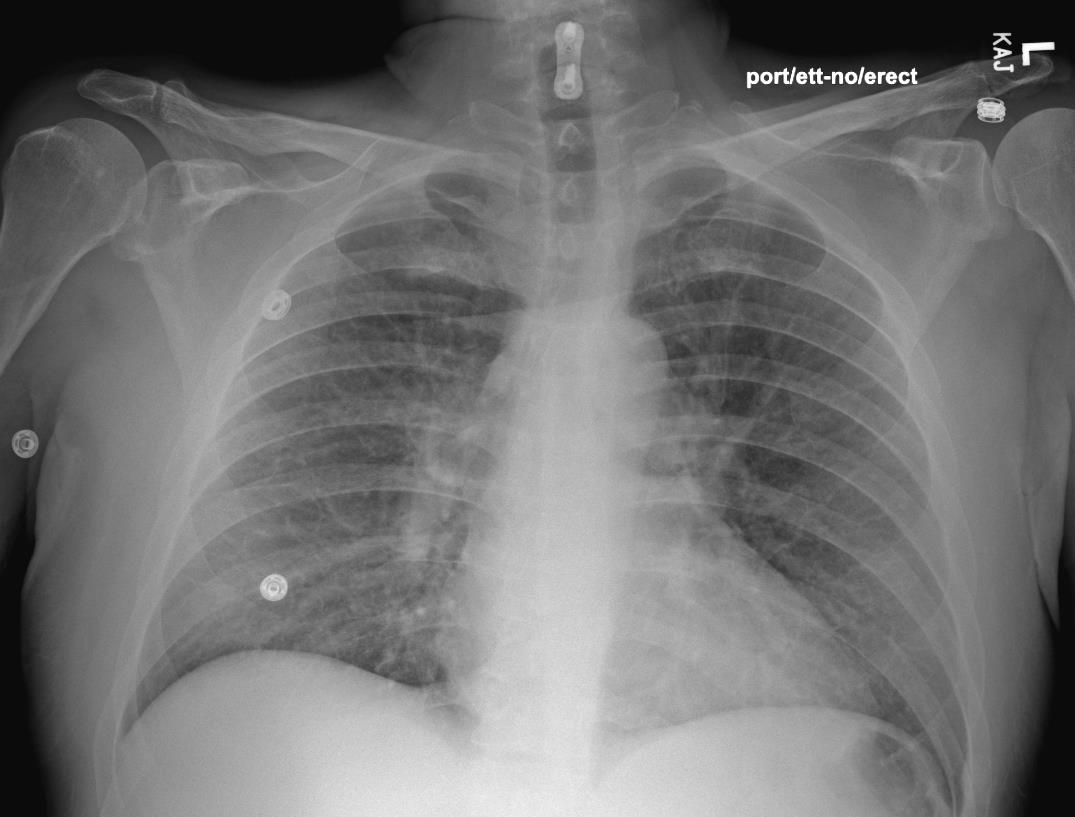

The right hallux wound (approximately 1.5 cm x 2.0 cm) had purulent, dishwater-like drainage with malodor, crepitus, and proximal spreading cellulitis with streaking. Clinically, the wound probed deeply to the underlying bone. The patient denied allergies to medication, food, or other products. The patient had no previous history of smoking. We started empiric vancomycin and piperacillin-tazobactam antibiotics for broad-spectrum Gram-positive and Gram-negative aerobic and anaerobic coverage. X-rays of the right foot revealed gas in the first interspace of the right foot with concern for osteomyelitis of the base of the second proximal phalanx. A preoperative chest X-ray (see image to left) showed no interstitial edema or pneumothorax, and EKG demonstrated sinus tachycardia. The patient underwent an emergent incision and drainage of the right foot, tolerating the procedure and anesthesia well without apparent complications. Multi-team based staged approach was utilized to attempt limb salvage with definitive right foot trans-metatarsal amputation (TMA) to follow once achieving resolution of the gaseous infection.

Infectious disease recommended broad-spectrum antibiotic coverage with vancomycin, clindamycin, piperacillin-tazobactam, and levofloxacin due to concern for Aeromonas species from freshwater exposure. Unexpectedly on postop day 3, the patient started complaining of respiratory discomfort and overall body swelling. The patient had new-onset dyspnea, hypoxemia, hydrocele, and edema, resulting in placement on a BiPAP machine. Laboratory investigation revealed leukocytosis, with a white blood cell count of 19.1×109/L (normal range 4×109/L to 11×109/L) with normal peripheral absolute eosinophil count of 0×109/L, and lactate level of 0.9 mmol/L. His arterial blood gas pH was 7.48 (normal pH 7.35 to 7.45), partial pressure of O2 77 mmHg (normal greater than 70-125 mmHg), partial pressure of carbon dioxide 26 mmHg (normal 35 mmHg to 45 mmHg), and calculated bicarbonate of 22 mmol/L (normal 23 mmol/L to 28 mmol/L). A repeat chest X-ray (see image to left) revealed new onset of pulmonary edema. A new computed tomography (CT) of the chest (see image below) showed diffuse ground-glass opacities with small pleural effusions and diffuse subpleural sparing, attributable to pulmonary edema with possible pneumonitis.